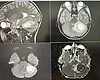

– В экстренное приемное отделение 7 марта поступил мальчик восьми лет с жалобами на рвоту, боль в животе, слабость, вялость, температуру. Хирурги исключили патологию по своему профилю. Но так как симптомы не проходили, было принято решение сделать МРТ головного мозга. Во время исследования у пациента был обнаружен абсцесс мозжечка, что встречается в практике врачей достаточно редко. Нашим коллегой-нейрохирургом Эдуардом Федоровичем Сырчиным была проведена первая часть операции – вскрытие абсцесса. Далее в операционную были приглашены мы. С первого взгляда было понятно, что это пациент именно по нашему профилю – в ухе виднелся гной и был характерный запах, – рассказала врач-оториноларинголог Детской областной больницы Надежда Стрижова.

У пациента был диагностирован отит, он проходил лечение по месту жительства, но заболевание прогрессировало. В итоге из-за скопившегося гноя произошел абсцесс, который и потребовал хирургического вмешательства. Вторым этапом мальчику была проведена антромастоидотомия – операция, во время которой хирург делает разрез за ушной раковиной, вскрывает сосцевидный отросток и позволяет гною вытекать наружу. Во время оперативного вмешательства устанавливается дренаж с целью дальнейшего промывания полости. После этого юный пациент находился в больнице, где ему проводилось дальнейшее лечение. С улучшением он через месяц был выписан домой.